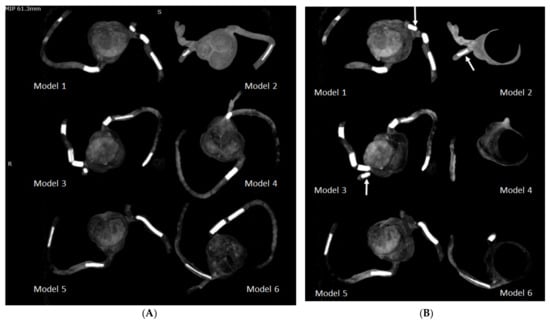

Figure 8 demonstrates coronal and oblique MIP images showing these calcified plaques in the coronary artery models, while Figure 9 presents VR images with window width changed. These 2D and 3D images clearly demonstrate the calcified plaques in the coronary arteries.

Figure 8.

Maximum-intensity projection (MIP) images showing the calcified plaques in six 3D-printed coronary models. (A) Coronal MIP view showing these calcified plaques. (B) Oblique MIP view showing the plaques more clearly in the left circumflex coronary artery (arrows) in model 1 (plaque 3), model 2 (plaque 6), and model 3 (plaque 11).